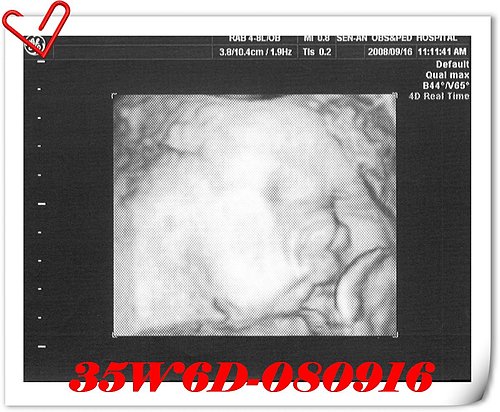

小寶体重:3,212g→3,297g 大肚婆体重:73.8kg→73.5kg

產檢前最擔心的莫過於上週被醫生說的~小小人已算是巨嬰這件事,這週很多甜的及零食都只能看不敢多吃,連茶品都只敢點:不冰,不糖,偶爾想解放一下也只敢:不冰,少少少糖。孕期後期除了頻尿、走路有點痛及走路姿勢無法再受控制外,最痛苦的還是飲食上的控制,醫院的體重計像嚴厲的判官,站上去之前心裡總要皮皮挫的看著那串跳動的數字,增加太快了,立刻會被一旁的護士判下重刑,控制得宜又立即得到緩刑,不過通常我都會因為心理得到暫時的舒緩而放縱自己,所以很快的在下次產檢前再度變成重刑犯就是了。

這週小小人的體重沒有增加太多,心裡稍稍的鬆一口氣,但增加的體重也太怪了點,後期的寶寶不是成長的很快嗎?怎麼我家小寶這週只長了85g的肉

離開診間前,還是鼓起勇氣問吳醫師關於無痛分娩的事(至今已忘了吳醫師給的是什麼答案了,其實自己很努力的想不做無痛,但還是怕陣痛一起,失去最後的毅力時會要求打無痛,於是多嘴的問了一問)。如果臨時要生了,而當天沒有吳醫師的診,他是否會幫我生產?吳醫師的答案是讓人安心的。還記得最後一個問題是,超音波寶寶的體重誤差值大概有多少?吳醫師說,超音波的誤差多少都會有,他不忘鼓勵我,妳可以的,要相信自己,多運動,多爬樓梯,隨時要生都可以了…